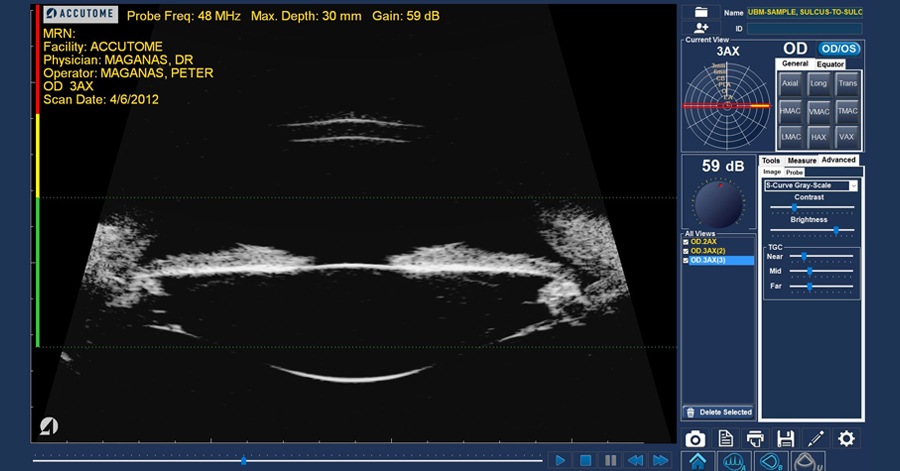

반면, 초음파생체현미경검사(UBM :Ultrasound BioMicroscopy)이라하여,

주파수를 더 높여 50-100MHz의 high frequency 해상도를 가진 초음파를 이용하여,

구조를 살필수 있는 해상력을 높여 50um (0.05mm) 까지의 구조물들을 구분할수 있습니다.

해상도가 높아진 대신 초음파가 깊이까지 침투하지는 못하기 때문에,

전안부조직, 혹은 망막의 주변부 즉 평면부 망막까지는 관찰할수 있습니다.

<UBM으로 관찰한 전안부 소견들>

UBM은

홍채에 가리는 홍채의 뒷부분까지 관찰이 가능하지만,

누운 자세에서 촬영해야하고,

눈에 직접 Probe가 접촉한 상태에서 측정을 해야합니다.

초음파가 공기를 통과하여 측정할 수가 없기 때문에, 환자가 누운 상태에서 눈에 깔대기를 씌우고 그사이에 물을 채운상태에서 Probe를 각막이나 공막에 대고 측정을하게됩니다. 즉, 직접 눈과 접촉한다는 점이 단점입니다.

검사자의 숙련도와 매우 밀접한관계가 있다는 것 역시 단점입니다.